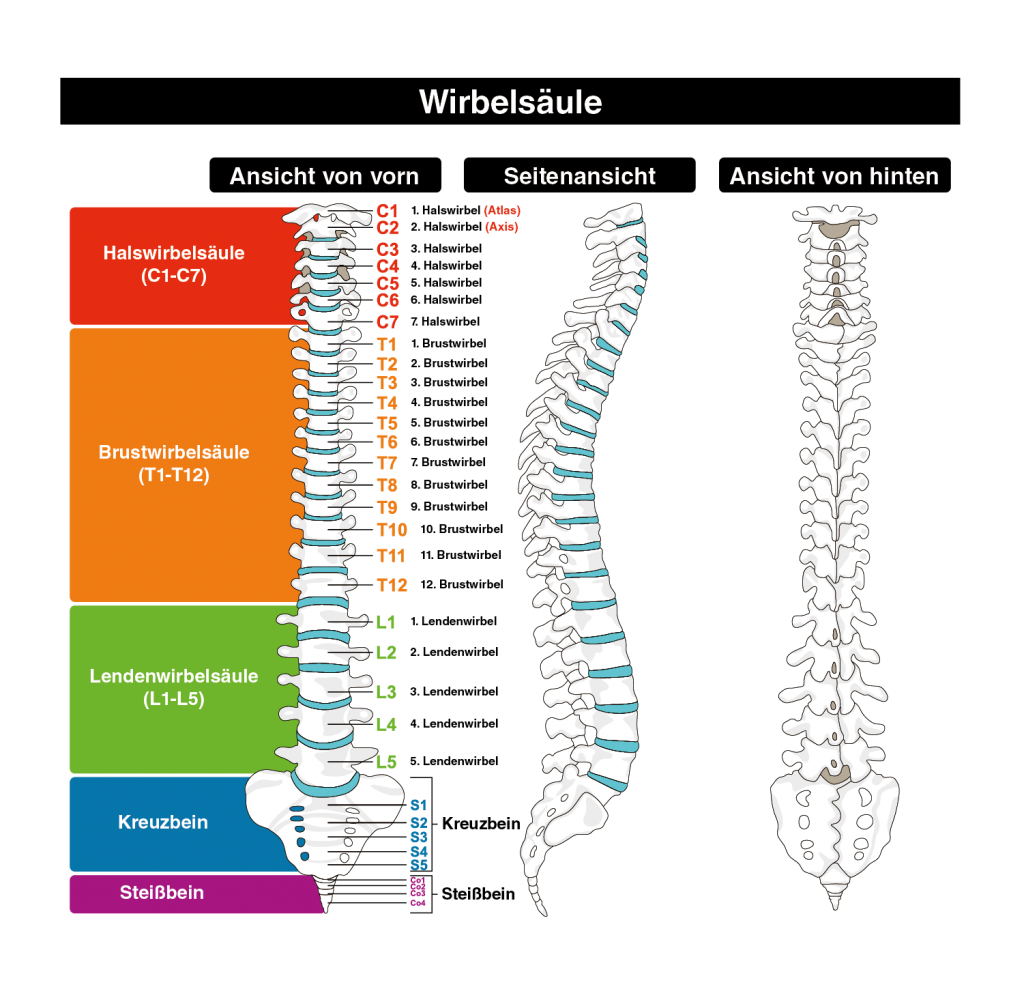

:background_color(FFFFFF):format(jpeg)/images/article/de/wirbelsaule/a1wjCWbEAeBhCqqodBbjHQ_Wirbels_ule_von_dorsal.png)